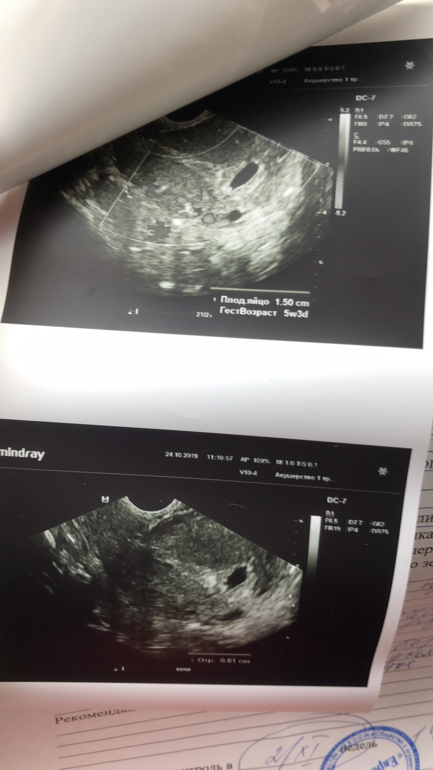

УЗИ, КТГ, доплер, скрининг, ХГЧ и другие анализыМилые,посмотрите ... мне врач нашла одно плодное яйцо и пустое говорит , срок по месячным 5.3 ,но дома я начала рассматривать снимки с узи и вот подумала ,не похоже ли это на 2 ПЯ ?

Вот снимок 2ПЯ в 5 недель 5 дней. При перемещении датчика контуры становились четкими. Который выше 15мм, который ниже 8мм. Может не стал специалист говорить "из благих побуждений", типа, чтоб не переживала, если маленькое ПЯ редуцируется. А, может, и правда, не ПЯ это вовсе(((

Ну я не переживаю на счёт эмбриональный,уверена что он появится . Меня смущает образование,похожее на второе яйцо )

Не знаю, что сказать. Ну с одной стороны похоже, но с другой контуры не такие четкие как у ПЯ, разница в размере большая. Мне кажется она бы сказала, если бы это было ПЯ.